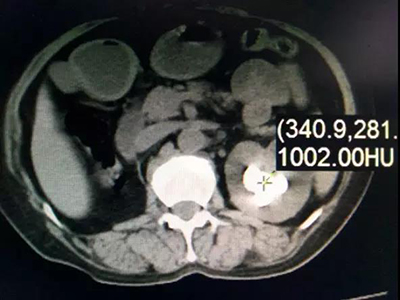

入院后彩超检查显示:左肾窦内可见数个大小不等的结石,最大的2.6 x1.9厘米,左输尿管上段距肾门2.5厘米处可见一大小约1.9厘米的结石。肾盂静脉造影显示:左肾及左侧输尿管上段多发结石,伴左侧肾盂、肾盏扩张;右肾缺如。CT检查显示:左肾肾盂、肾盏多发不规则高密度影,部分形成肾盏铸型,边缘锐利,CT值780—1500HU,左肾多发类圆形低密度影,右肾缺如。心电图检查:T波改变。胸片提示:两肺纹理增多、心影增大。经详细检查最终确诊为:左肾多发结石、左输尿管多发结石、左肾多囊肾、右肾缺如、高血压Ⅱ级。